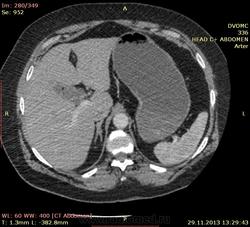

Пациентка 66 лет. В 2010 году мастэктомия слева - Cr II B ст., псориаз. Я нашел: образование нижнего полюса правой почки, образование в антральном отделе желудка по малой кривизне, киста яичника слева...в желчном пузыре много газосодержащих камней(?), лимфоузлов вроде не видно. Всё, кроме образования желудка находили ранее на УЗИ да на МРТ. Коллеги, посмотрите, можт я чё пропустил или неправильно понял. Какие мысли по поводу образований - особенно желудка(GIST? mts?)  DICOM здесь http://files.mail.ru/2C4F7CA79A884D37B3C86FF69C3D8D67

Мне кажется, что маловато контраста на вес пациентки. Почечно-клеточная (как более вероятная) карцинома правой почки, в стенке желудка написала бы мтс. Газосодержащие камни желчного пузыря. Кистовидное образование яичника. Киста печени, кисты почек. Дивертикулез толстой кишки. А что с жиром в грыже (вроде пупочная))) - наверное, последствие инфаркта сальника.